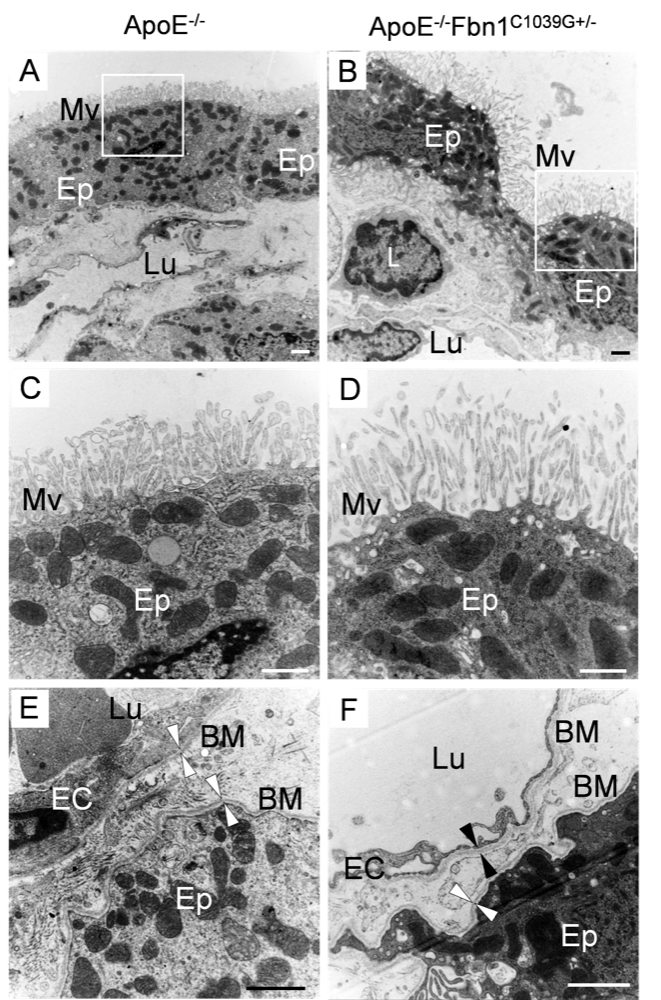

Chapter 4 Figure 7Morphological changes in the choroid plexus of ApoE-/-Fbn1C1039G+/- mice on TEM. In contrast to the adjacent and cubic epithelial cells of ApoE-/- mice (A), the epithelial cells of ApoE-/-Fbn1C1039G+/- mice appeared flattened and detached and showed ‘stretched’ microvilli at their surface (B). In ApoE-/-Fbn1C1039G+/- mice, leukocytes (L) were often observed adherent to the choroid plexus endothelium or even migrated into the choroid plexus parenchyma, having crossed the fenestrated endothelium and basement membrane (B). (C, D) Detail of the microvilli on the epithelial cells in (A, B). The microvilli on the epithelial cells of ApoE-/-Fbn1C1039G+/- mice appeared less dense and stretched compared to those of ApoE-/- mice. (E, F) Detail of the basement membrane (arrowheads, BM) in an ApoE-/- (E) and an ApoE-/-Fbn1C1039G+/- mouse (F). Ep=epithelial cell, Mv=microvilli, Lu=lumen of blood capillary, L=leukocyte, EC=endothelium, BM=basement membrane. Scale bar=1 µm.